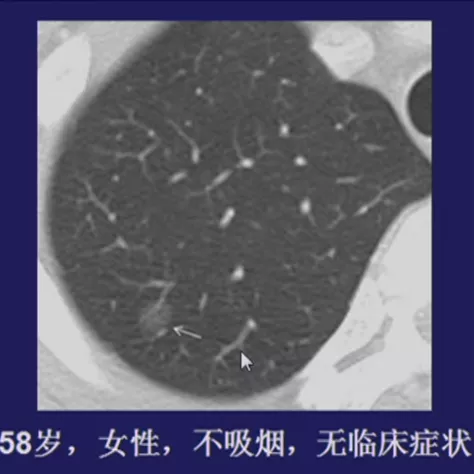

如上图所示,一般来说这么小的病灶我们可能忽略,但这个病人做了手术,不仅是恶性肿瘤,而且是微浸润腺癌。实际上我们在临床上要把这么多结节甄别出来,是十分具有挑战性的。病人一旦患有肺结节,也面临着很多问题,比如焦虑、心理压力等。所以我们既不能过度诊断,但也不能延误诊断。

微小肺结节(肺癌)的诊断价值?

我们刚才看到的征象都是比较典型的。如上图所示的小结节,什么征象都没有,判断为良性也很困难。刚才提到的那么多结节的特征,在微小结节中少见,价值有限。因此,如何提高微小结节的诊断水平是关键,因为在早期手术效果相当好。